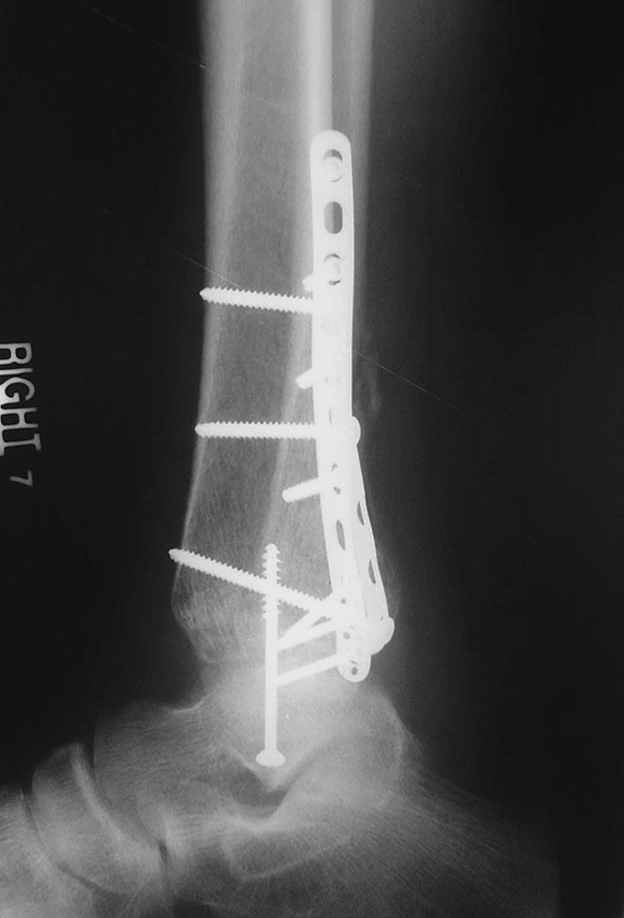

Re: ANKLE FRACTURE

Второй случай сделан из одного разреза

ЕЧ LISS plate, mininvasive approach - luxurous !

Вопрос практического характера - такой подход рутинный или при определенных показаниях и каких? Спрашиваю потому, что при потоке больных - закрытая голень, бедро, голеностоп и т.д. лучевая нагрузка должна быть немалая, каковы показатели дозиметра после такого операционного дня и при 2-3 операционных днях в неделю по 5-6 случаев (не считая ургентностей)?

На прямой проекции послеоперационного Рг макроскопически все выглядит очень анатомично, при микроскопическом ( :-)) ) рассмотрении можно все-таки заметить вальгизацию тарана, суставная щель в латеральном отделе сустава несколько уже , чем в медиальном при отсутствии латерального смещения тарана. У меня был аналогичный случай (без LISS , без мини доступа) с вальгусным наклоном тарана при восстановленном ankle mortise при последовательном наблюдении с интервалами в 6-8 недель в послеоперационном периоде отмечалось прогрессирующее сужение суставной щели в латеральном отделе сустава, закончившееся посттравматическим ОА, к счастью боли умеренные, купируемые аналгетиками или своими эндорфинами:-))(активная пациентка, у которой нет времени на болезни....) Какова жизненная ситуация в приведенном вами случае? И последнее, что я хотел бы прояснить для себя - фиксация внутренней лодыжки: я обычно комбинирую фиксацию компрессирующим винтом со спицей - по идее ротационная стабильность должна быть лучше, чем один винт, каковы ваши наблюдения в этом плане?